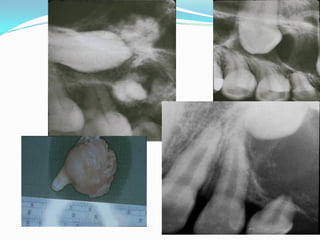

Odontoma

 The tumors in which

odontogenic differentiation is

fully expressed are the

odontomas. In these tumors,

the epithelium an

ectomesenchyme realize their

potential and make enamel

and dentin respectively.

 As a result, these tumors are

mostly radiodense.

 In the compound odontoma,

multiple small and

malformed tooth-like

structures are formed

creating a “bag of marbles”

radiographic appearance

 The odontoma is the most common odontogenic

tumor.

 It is not a true neoplasm but rather is considered

to be a developmental anomaly (hamartoma).

 Two types of odontomas are recognized:

 Compound: this type of odontoma is composed of

multiple small tooth-like structures.

 Complex: this lesion is composed of a conglomerate

mass of enamel and dentin, which bears no anatomic

resemblance to a tooth.

Odontoma: Radiographic Features

 Early lesions are radiolucent with smooth, well-

defined contours.

 Later a well-defined radiopaque appearance develops.

 The compound type shows apparent tooth shapes

while the complex type appears as a uniform opaque

mass with no apparent tooth shapes present.